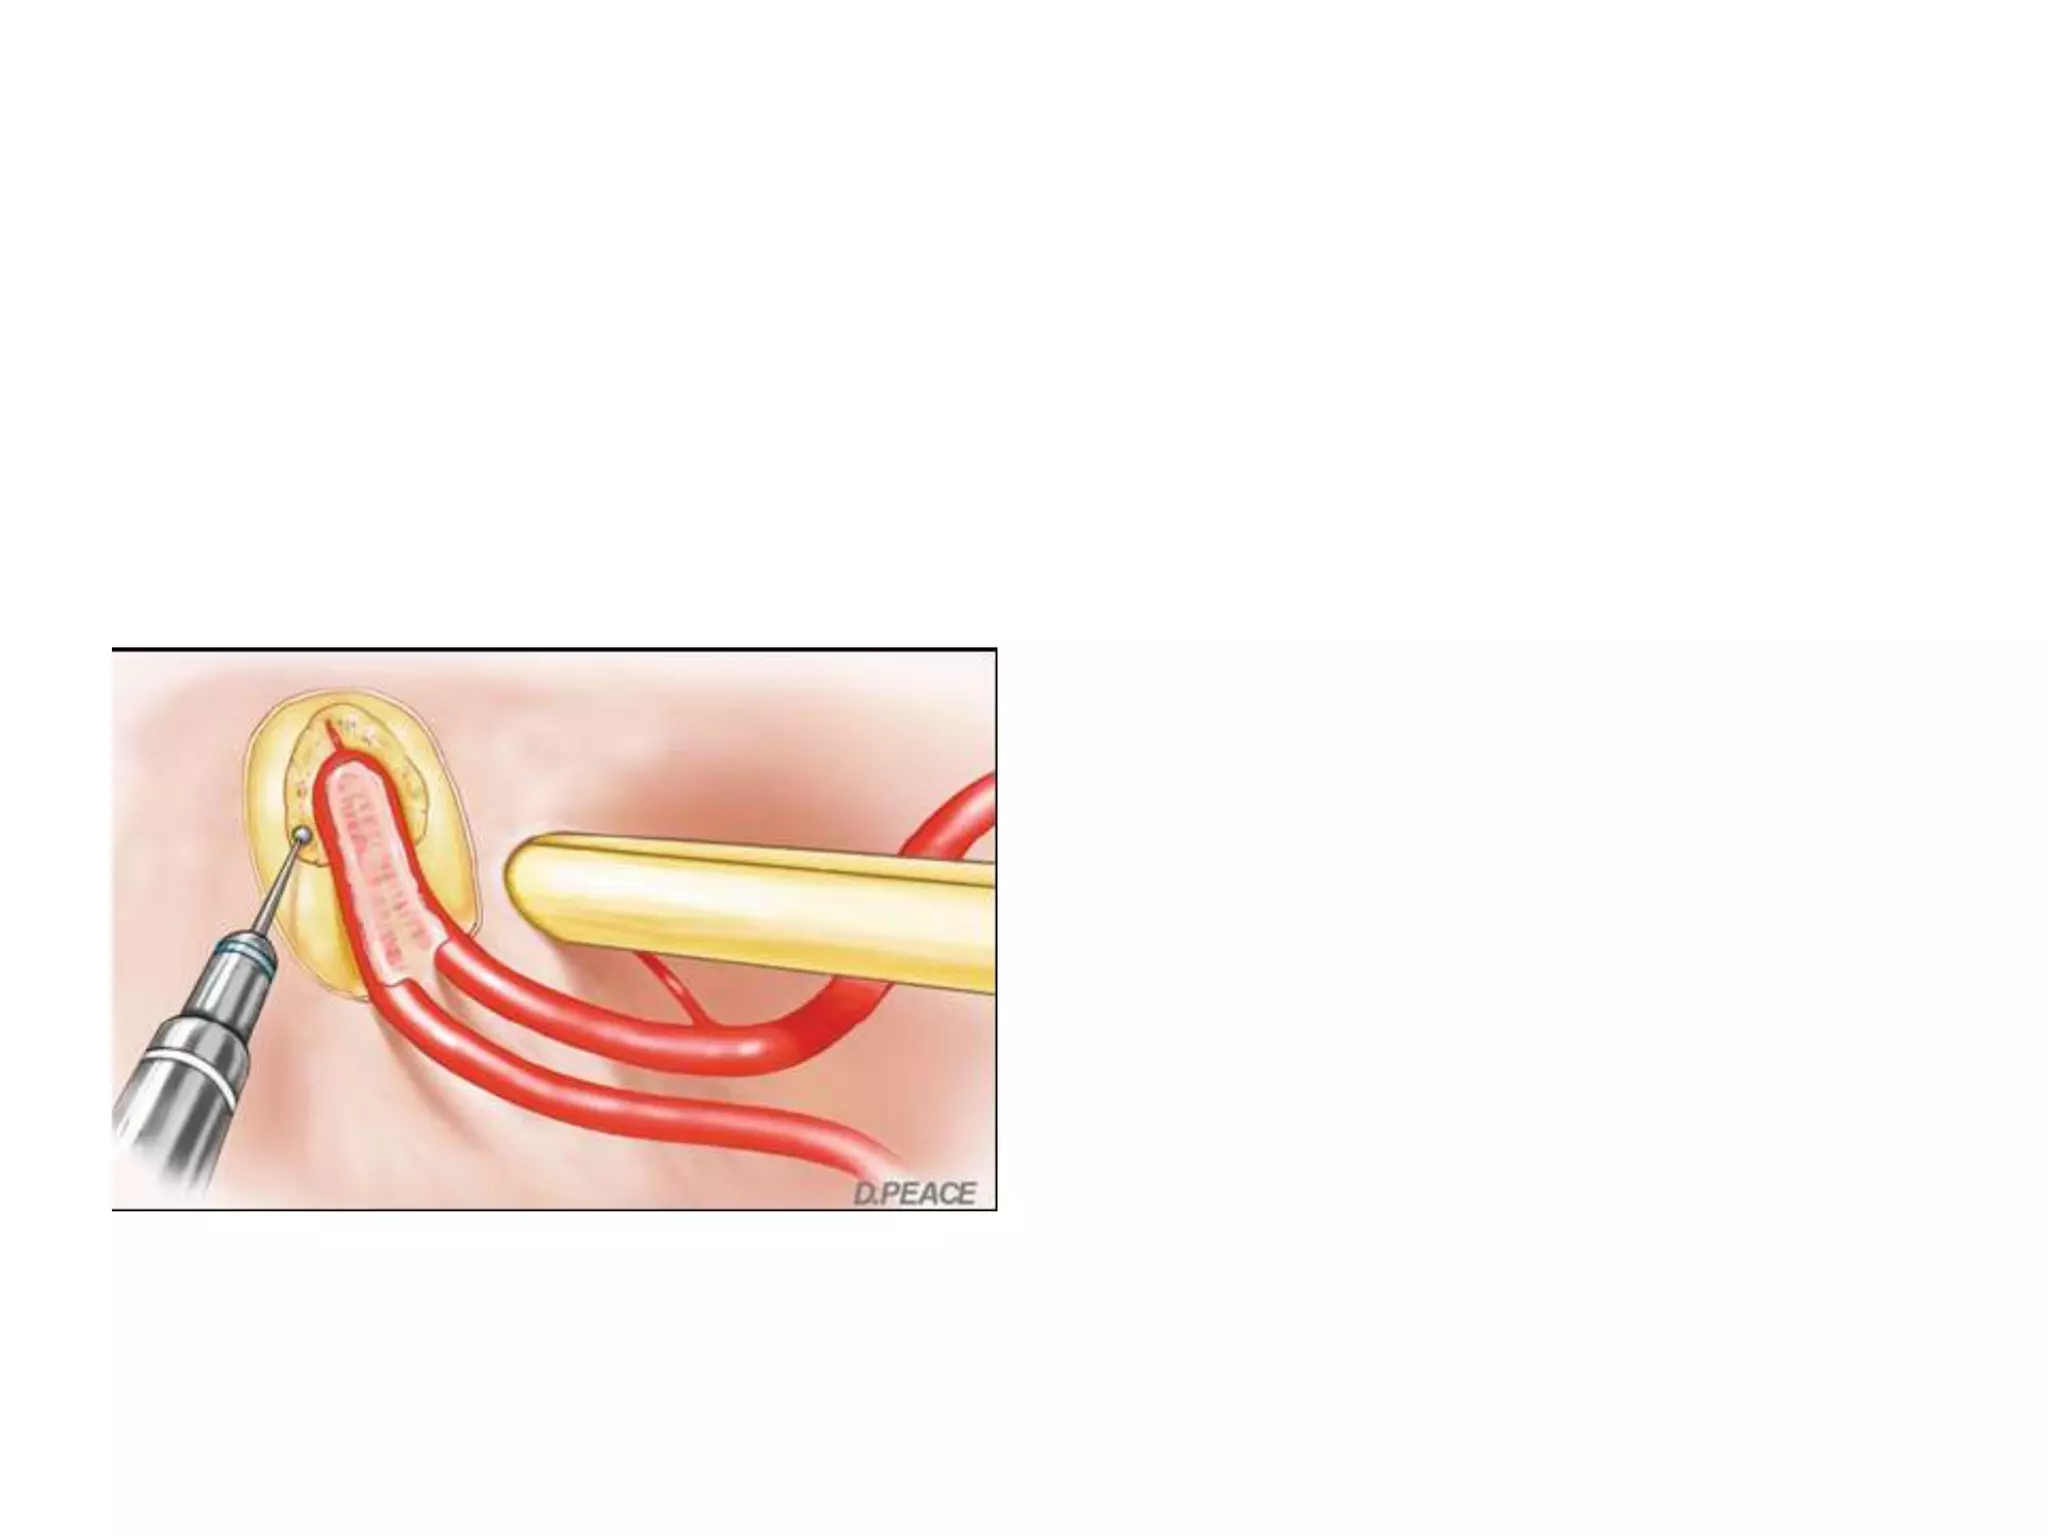

Division of PComA